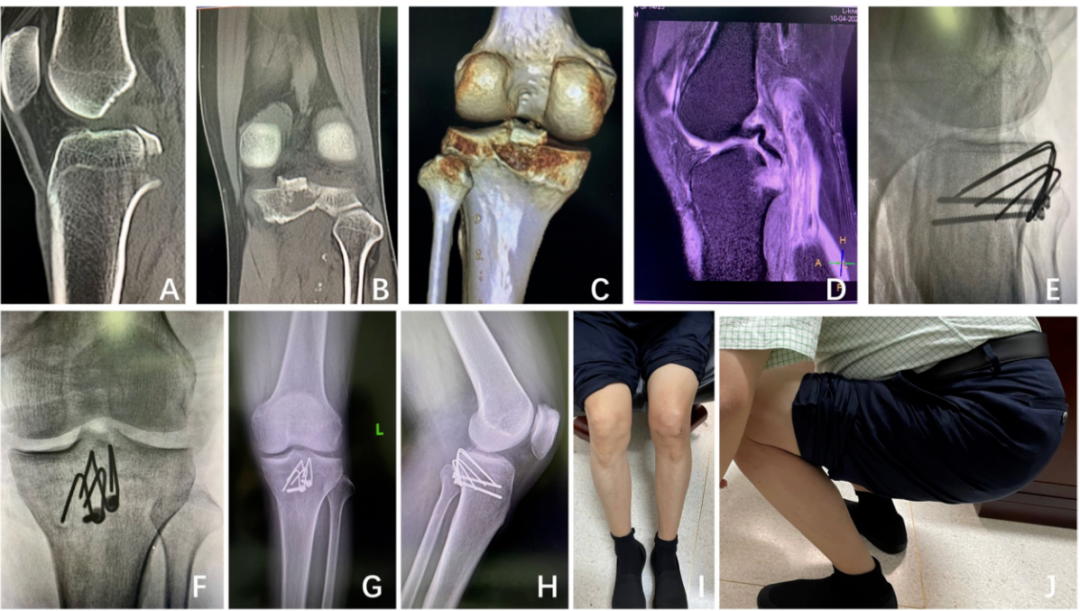

使用自制的倒L形后内侧入路和针钩固定技术治疗后交叉韧带(PCL)撕脱骨折,可以获得满意的临床和放射学效果。此外,这种由K线制成的针钩成本低廉,减少了费用,是一种实用且值得推荐的方法,尤其适合社区医院使用。 参考:Guo Q, Li X, Tang Y, et al. Homemade pin-hook for surgical treatment of posterior cruciate ligament avulsion fractures. BMC Musculoskelet Disord. 2022, 21;23(1):929.